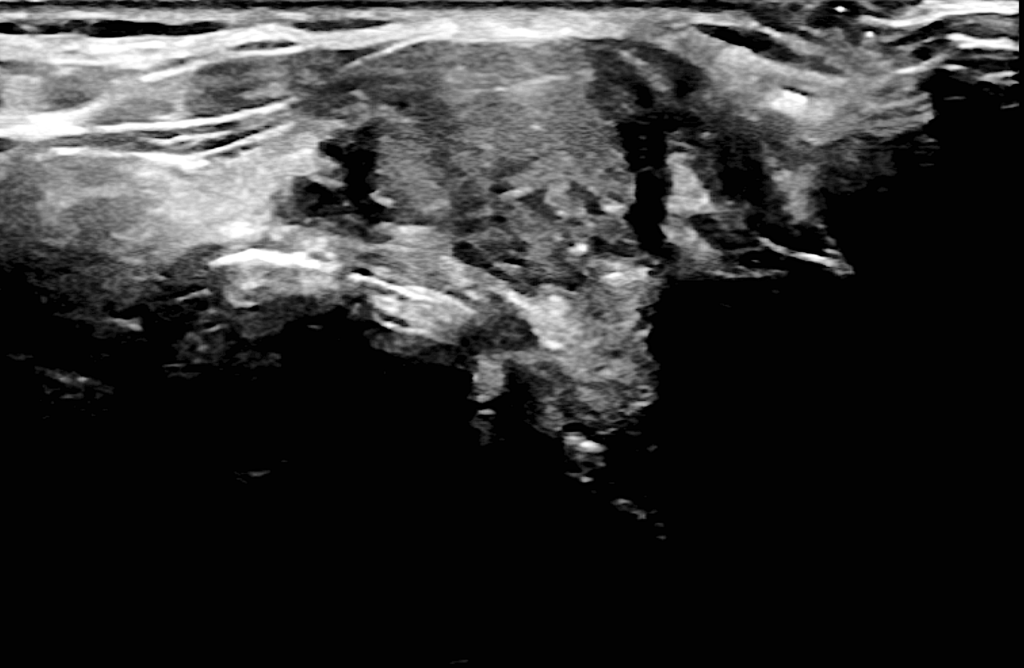

Επικίνδυνος όζος στον αριστερό λοβό του θυρεοειδούς αδένα σε νεαρή γυναίκα ασθενή μας, ο οποίος συγκεντρώνει πολλαπλά ύποπτα χαρακτηριστικά (υπόηχος όζος, ανώμαλα όρια με πιθανή διάσπαση της κάψας του θυρεοειδούς), η παρακέντηση του οποίου αποκάλυψε την παρουσία θηλώδους καρκίνου του θυρεοειδούς (Bethesda VI).